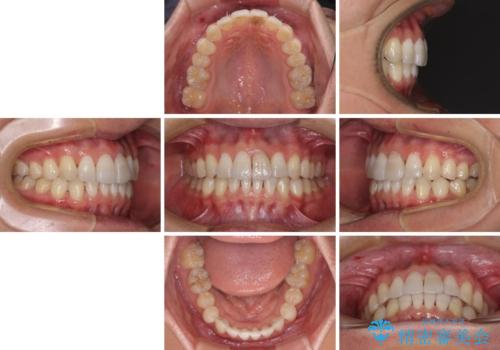

- 前歯のデコボコを治したいとのことで来院された患者様です。

上下顎ともに歯列全体の後方移動とIPR(歯と歯の間を削る)によってデコボコが解消するように設計し、インビザラインにより治療を行うこととしました。

矯正治療後、前歯の形と色が気になるとのことでしたが、大分前に失活している(神経が取り除かれている)歯であり、その影響で変色しているため、オールセラミッククラウンによる補綴治療をおすすめいたしました。